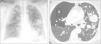

Nódulos pulmonares múltiples bilaterales

Multiple bilateral pulmonary nodules